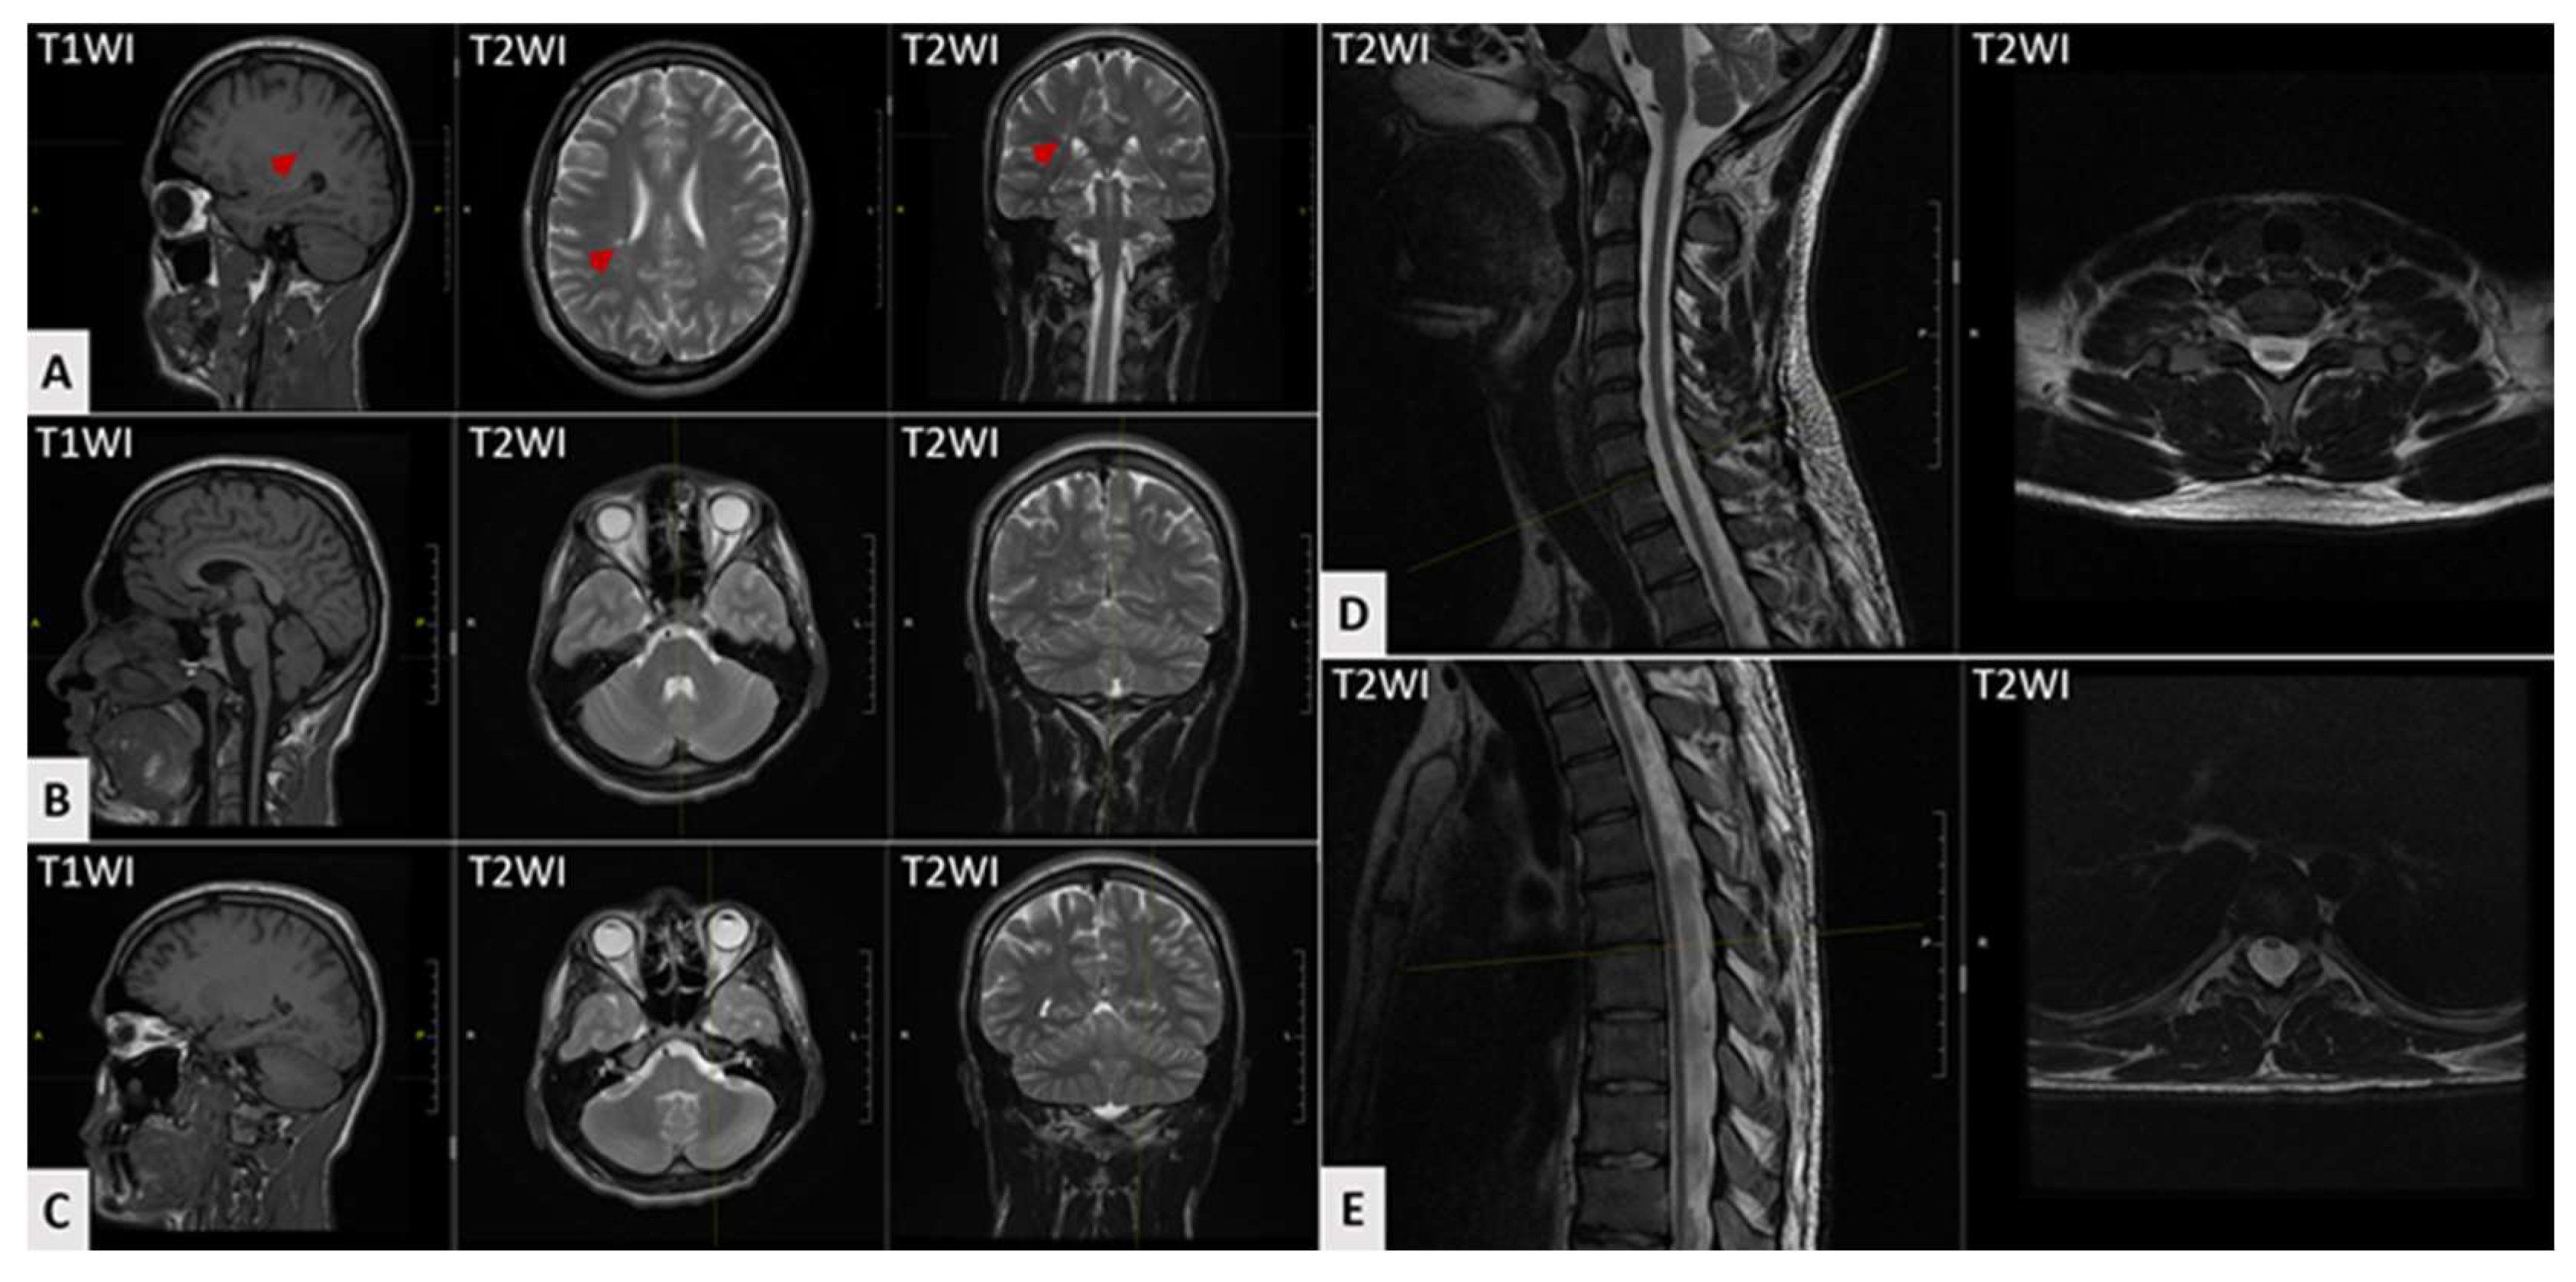

| Brain and spinal cord MRI | |

| MRI: cerebral atrophy | 28% (5/18) |

| MRI: cerebellar atrophy | 17% (3/18) |

| MRI: T2-hyperintensities at cerebral white matter | 5% (1/18) |

| MRI: T2-hyperintensities at thalamus | 5% (1/18) |

| MRI: spinal cord atrophy | 44% (8/18) |